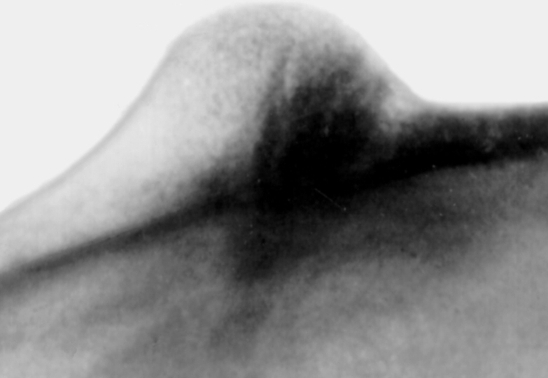

Опухоль, происходящая из хондробластов, по своему внешнему виду напоминает скопление дифференцированной хрящевой ткани. Эта опухоль тоже чаще всего встречается у молодых людей. Возникает на суставных поверхностях, нередко поражает плечевой пояс, а также коленный и тазобедренный суставы.